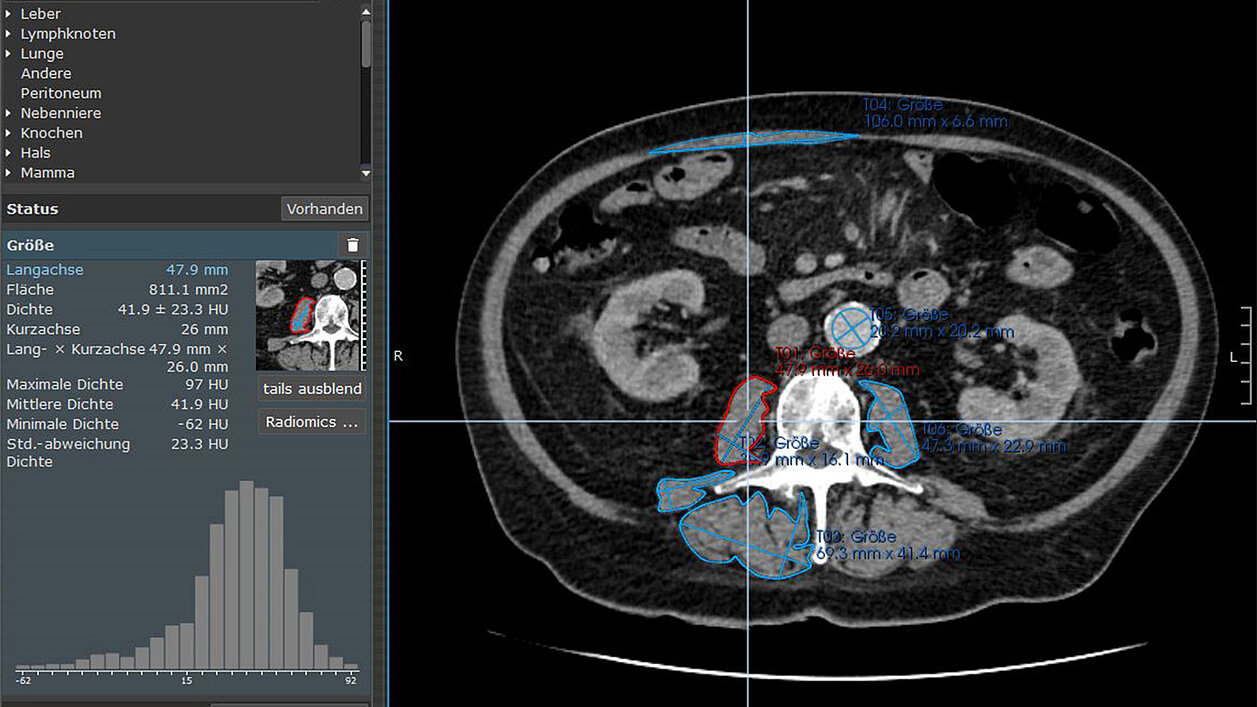

mint Lesion™ wurde für die Segmentierung der Skelettmuskulatur und die Extraktion von radiomischen Merkmalen verwendet. Die Forscher haben den Musculus psoas major, den Musculus erector spinae und den Musculus quadratus lumborum segmentiert und einen umfassenden Satz von 85 radiomischen Merkmalen aus jedem analysierten Muskel extrahiert.

Die Studie nutzte diese radiomischen Merkmale, um eine detailliertere Bewertung der Skelettmuskeln zu ermöglichen. Die Merkmale wurden in verschiedene Typen eingeteilt:

- Formmerkmale, die die Geometrie und Morphologie des segmentierten Skelettmuskels beschreiben, z. B. Volumen, Sphärizität und andere formbezogene Parameter;

- Merkmale erster Ordnung, die die Verteilung der Voxel-Intensitäten innerhalb der definierten Region of Interest (ROI) darstellen, z. B. mittlere Intensität, Median-Intensität und Standardabweichung;

- Merkmale höherer Ordnung, die über einfache Statistiken hinausgehen und komplexere Analysen der Voxelwerte beinhalten, welche die Anordnung und die Beziehungen zwischen den Voxelintensitäten innerhalb der ROI widerspiegeln - z. B. Clustertendenz, Differenzentropie und Summe der Entropie.